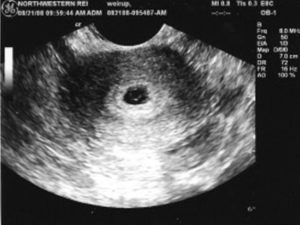

image

Если врач во время ультразвукового исследования сообщает, что видит в полости матки плодное яйцо — женщину можно поздравить, ведь через 9 месяцев она станет мамой. Установить наличие плодного яйца можно уже на 7-9 день задержки менструации.

Если плодное яйцо в матке – значит беременность нормальная, маточная. Специалист сразу же определит размер плодного яйца, его форму и расположение. Кроме этого, обратит особое внимание, не имеет ли место отслойка или другие патологические состояния.

Плодное яйцо – овальное или круглое тело диаметром в несколько миллиметров. Диаметр плодного яйца замеряется во время первого же УЗИ. Учитывая его размеры, специалист может установить срок беременности. Но в некоторых случаях погрешность в определении составляет 1-1,5 недели. Поэтому врач, пытаясь установить срок, учитывает также показатели копчико-теменного размера.

плодное яйцо выглядит как образование в виде шара или овала. Уже в 5-6 недель желточный мешок, который обеспечивает питание эмбриона и выполняет кроветворную функцию на ранних стадиях развития эмбриона, похож на пузырек внутри полости плодного яйца.

Размер плодного яйца на этой стадии беременности составляет от 1,5 до 2,5 сантиметров. Рассмотреть зародыш в это время уже можно. Он выглядит, как пятимиллиметровая полоска, расположенная рядом с желточным мешком. И хотя определить, где у зародыша какая структура и часть пока невозможно, сердцебиение уже регистрируется.